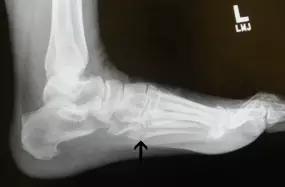

14.第五跖骨骨折

第五跖骨基底部骨折的不同类型:Stress 骨折;Jones 骨折:第五跖骨基底部以远 1 英寸内的骨折称为 Jones 骨折; Avulsion 骨折。

(来源:Radiopaedia)

Stress 骨折(来源:OrthoInfo-AAOS)

Jones 骨折正位片(来源:Radiopaedia)

Jones 骨折斜位片(来源:Radiopaedia)